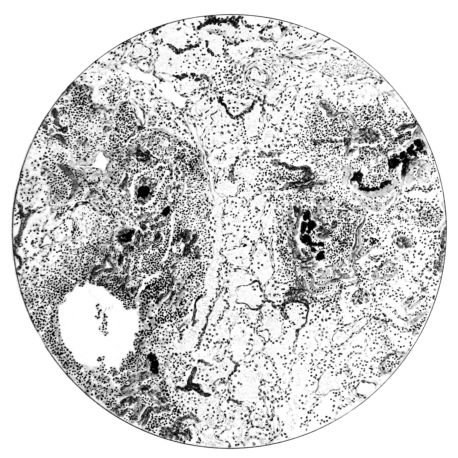

FIG. I. AUTOPSY NO. 99. ACUTE HEMORRHAGIC AND ULCERATIVE LARYNGOTRACHEITIS.

Early in the disease the congestion and the hemorrhages that have been described in the mucous membrane of the nasopharynx (14 and 94) are also conspicuous features in the lining of the trachea and bronchi (Fig. I). This membrane is swollen, turgid, red, and covered by a copious, mucous exudate which may be clear, but much more frequently is blood-stained or opaque and yellowish in color. The blood, variable in amount, may be fresh and red; and after the mucous exudate on the surface is removed, more intense red foci stand out on the congested base (47, 90, 157). Frequently, as the bronchi are approached, the red color of the mucosa becomes more intense and may have a garnet tinge. Membranes such as are encountered in the more usual necrotizing inflammatory processes, like diphtheria, have not occurred in the trachea and larger bronchi in this series (108, 128, 157).[3] The exudate peels off readily, and as indicated above, leaves a velvety red surface, 14dotted here and there with darker or more intensely red foci. Small ulcerations of the mucosa occur, but are inconspicuous (82, 156). As the finer ramifications of the bronchi are approached, the accumulation of the exudate in their lumina becomes more and more marked, and on cross section of the lung, they often stand out conspicuously on account of their increased size and projecting, seromucous, blood-stained content (101, 149, 162).